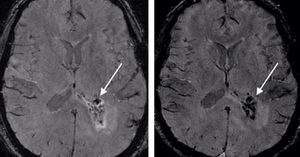

Hemorrhages can be easily distinguished from veins if SWI is performed both before and after administration of contrast agent. Blood vessels will change their signal intensity due to the contrast agent, but signal intensity from hemorrhage will not change. Fig (left) Precontrast SWI shows a small hemorrhage inside the tumor (arrow). (right) In postcontrast SWI, a new hypointense signal intensity appears after contrast agent injection, which indicates the presence of intratumoral vessels; the signal intensity from the hemorrhage inside the tumor remains unchanged (arrow). Mittal et al. 2009